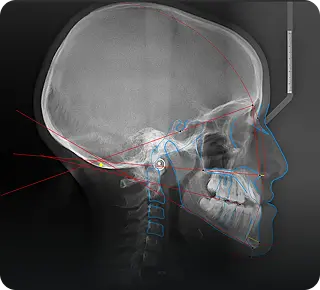

Board-certified reports for implants, TMJ, and airway with systematic incidental finding screenings.

Accurate, rapid diagnostic analysis for panoramic, cephalometric, and periapical radiographs to support treatment planning.